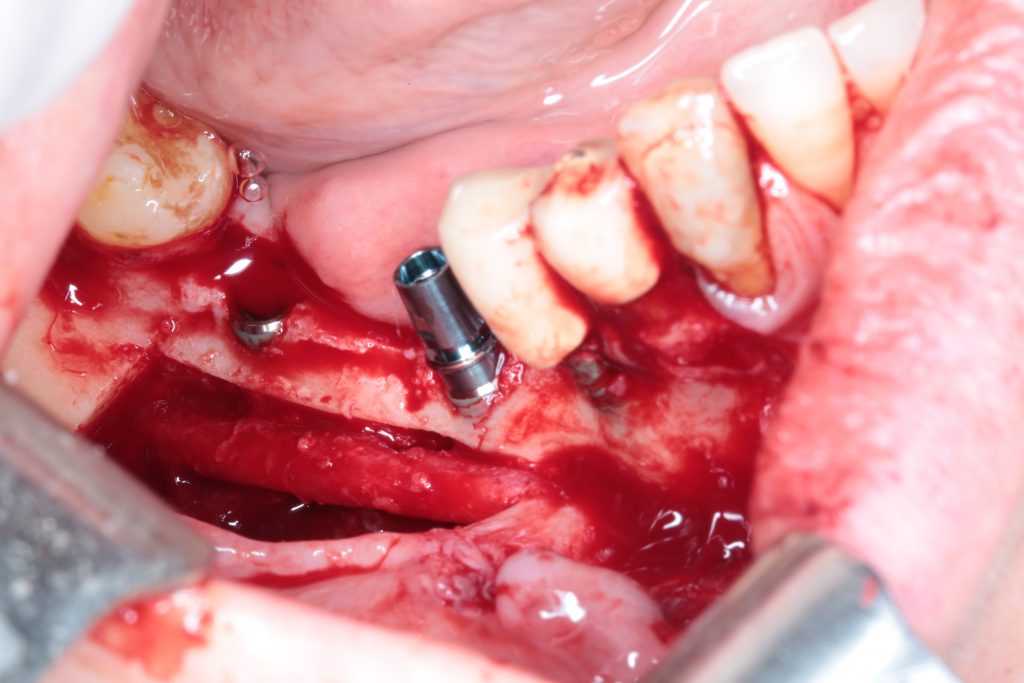

- Nerve Lateralization + Bone Augmentation

A bone block is harvested from the retromolar area and then split into two very thin bone blades. These blades will be used to restore the missing cortical walls.

Autogenous from chips, obtained with a safe-scrapper like this one, and a bone crusher, will be placed in the space created by those two thin bone blades.

The whole procedure is performed, if possible, through the already explained tunnel approach.

From an augmentation in the posterior mandible to an augmentation in the anterior region of the mandible to another one in the anterior area of the maxilla.

The longer and deeper the defect is, the more difficult the procedure is.